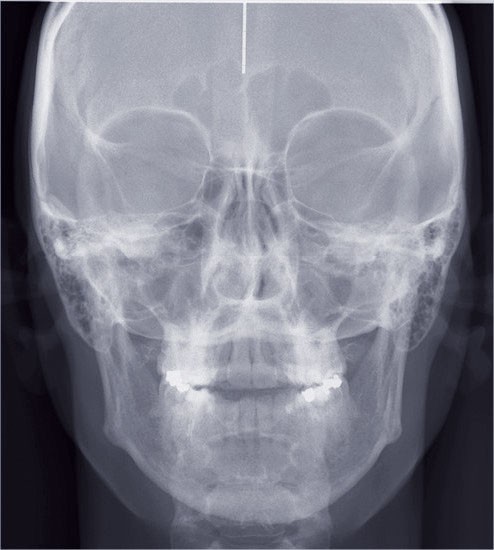

6 mois plus tard

L’esthétique faciale de la patiente s’est nettement améliorée (fig. 7, 8, 9 et 10). On remarquera la réduction du sourire gingival…